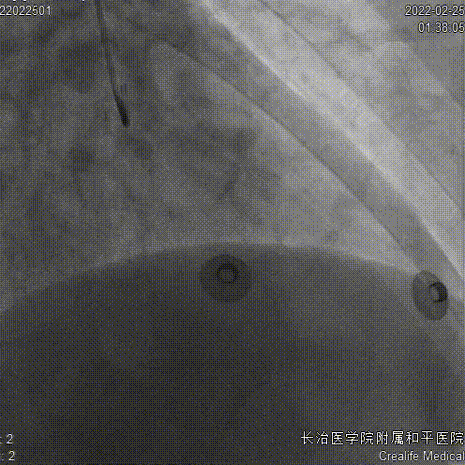

6FEBU3.5Guiding、Runthrough导丝、Sion导丝、2.0x15mm球囊

2.5x10mm切割球囊

药物球囊2.75x35mm、Telescope™导引延长导管

药物球囊定位、释放